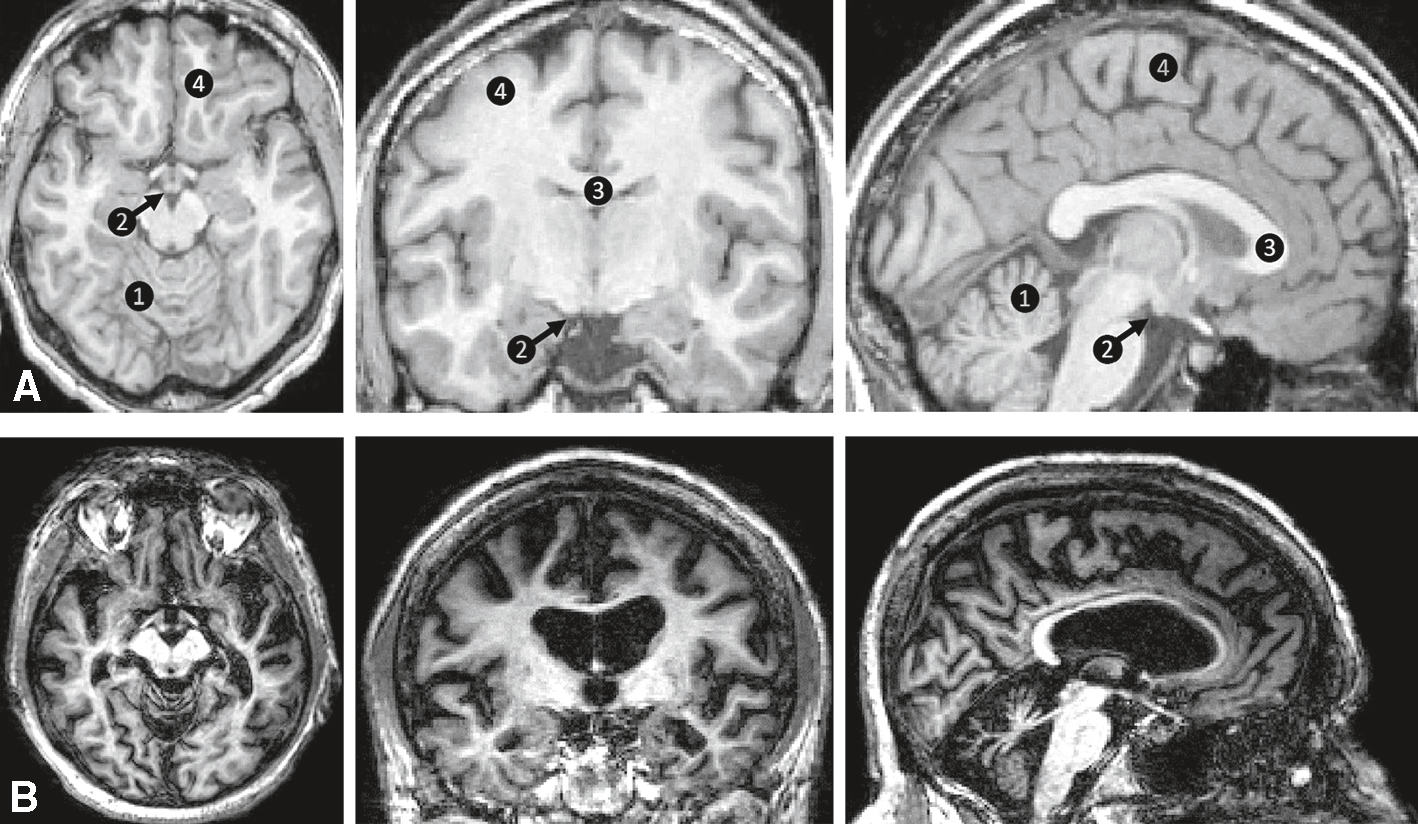

L’imagerie cérébrale objective parfois une atrophie des corps mamillaires (fig. 2.1).

Syndrome de Korsakoff. IRM T1 axiale (à gauche), coronale (au milieu), sagittale (à droite). 1. Cervelet. 2. Corps mamillaire (flèche noire). 3. Corps calleux. 4. Cortex. A. Sujet sain. B. Syndrome de Korsakoff : atrophie du cervelet, des corps mamillaires, du corps calleux et du cortex.

Sur les images en T1 pondéré, en séries axiales, coronales et sagittales (rangée A), on observe un hypersignal symétrique des corps mamillaires (repère 2) et du thalamus médian (repère 3), souvent atteint dans les encéphalopathies carentielles. L’atrophie des corps mamillaires est nette sur le plan sagittal, accompagnée d’un élargissement des sillons corticaux (repère 4), suggérant une perte de volume cortical diffuse. Le fornix (repère 1) paraît aminci, probablement secondaire à une dégénérescence transneuronale. En B, l’atrophie hippocampique est notable, avec des ventricules dilatés, caractéristiques d’un syndrome de Korsakoff chronique. Pas de rehaussement anormal ni de signe d’hémorragie active.